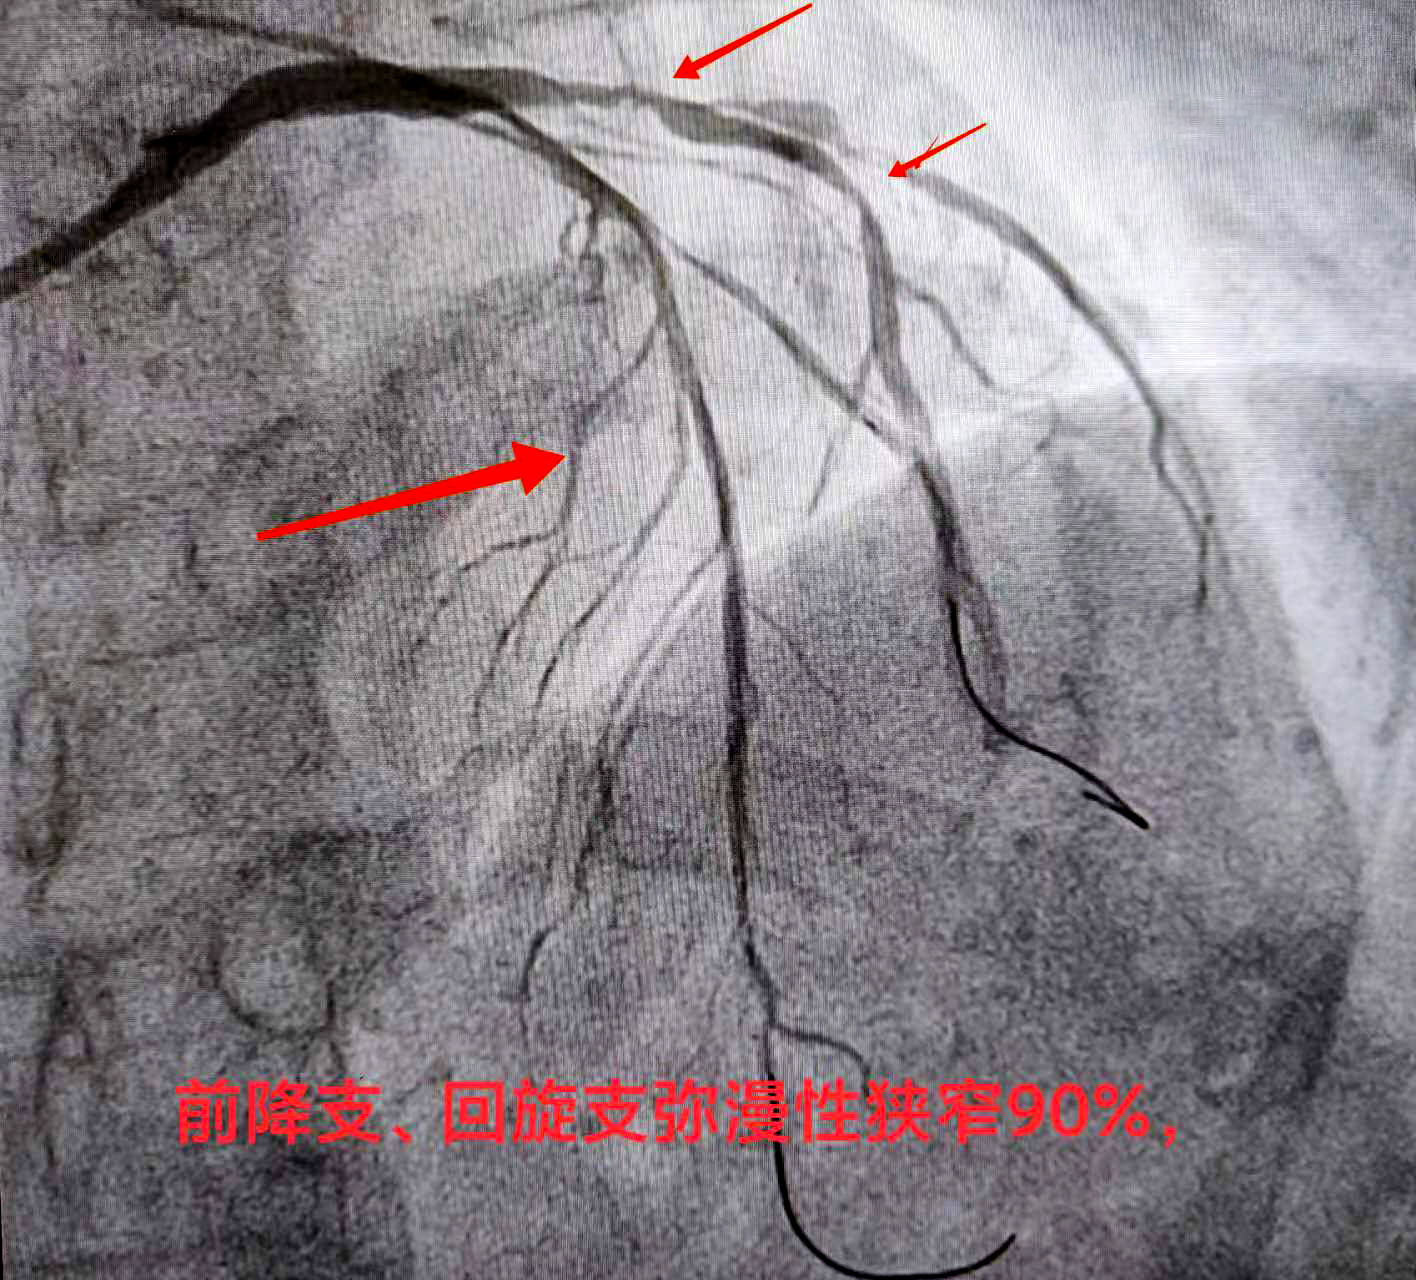

熊斌主任在接诊后立即为赵某做相关检查,结果显示严重三支病变——即为心脏供血的三条大血管前降支血管、回旋支血管、右冠状动脉,甚至包括左主干都存在狭窄病变,狭窄程度达90%以上,属于弥漫性狭窄病变。通俗地讲,就是赵某的冠脉血管近乎全都堵塞不通,血液无法顺畅供给心脏,这导致了心脏缺血,从而引起胸闷、胸痛、心慌气短等不适症状,严重者还会导致心肌坏死、心梗发生,严重威胁生命健康。

经检查,赵某恢复良好,身体状况符合再次开展介入的条件,因此医院很快为赵某安排了手术时间。“依据我们根据患者病情制定的治疗方案,这一次针对前降支血管开展支架介入。”熊斌主任介绍,根据赵某的血管具体情况,此次介入仍是在杨胜利教授的指导下,在赵某的前降支血管植入两枚药物洗脱支架,支架贴壁膨胀良好,血管得以顺利开通,血流得以恢复,而且支架上携带的药物也能起到预防支架内再狭窄的作用。同时,科室在脉络学说指导下,发挥中西医结合诊疗优势,在常规西药加支架治疗基础上加用通络药物,显著降低心梗支架术后心肌无复流发生率,改善心肌微循环血液灌注,保护心肌,减少心室重构,避免向慢性心衰发展,从而改善心梗支架植入患者的远期预后。

“通过两次支架介入,患者已实现狭窄血管再重塑,血流改善,心血管风险大大降低。”熊斌主任表示,待赵某恢复调养一段时间后,则可再针对回旋支血管进行介入开通,这将会进一步改善心脏供血,缓解相关不适症状。